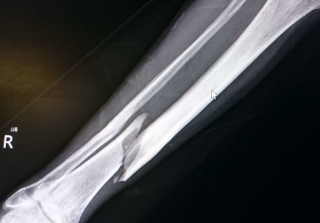

골절의 종류와 치료방법

뼈와 골절 오늘은 골절의 종류와 함께 치료방법에 대해서 알아보도록 하겠습니다. 골절(fracture)은 뼈의 연속성이 끊어지는 의학적 질환입니다. 뼈 골절의 상당 부분은 높은 힘의 충격이나 스트레스로 인해 발생합니다. 그러나 골절은 골다공증(osteoporosis), 일부...